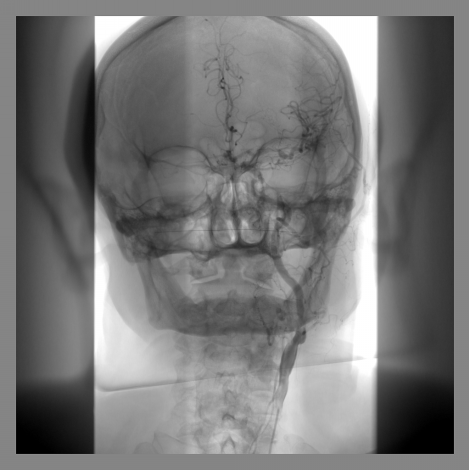

荧光造影图像